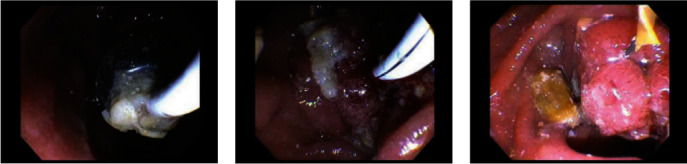

Introduction: Sump syndrome is a rare complication following bilioenteric anastomosis, most commonly following choledochoduodenostomy. This is only the third case in the literature of sump syndrome of the distal common bile duct (CBD) following end-to-side Roux-en-Y choledochojejunostomy (RYCJ). Case Presentation. A 69-year-old man with a history of end-to-side RYCJ for recurrent primary choledocholithiasis presented 3 years postoperatively with right upper quadrant (RUQ) abdominal pain affecting his quality of life. The work up revealed mild leukocytosis and computed tomography (CT) imaging that showed dilation of the distal CBD remnant. He underwent endoscopic retrograde cholangiopancreatography (ERCP) with the removal of large amounts of debris with initial resolution of his pain, but the pain recurred after several months and after two further ERCPs with only short-term resolution of pain, he eventually underwent an open distal CBD excision and the pain has since resolved.

Conclusions: This case report describes a rare case of sump syndrome following RYCJ that presented with abdominal pain alone. Sump syndrome may have a wide array of presenting symptoms, and the pathophysiology of sump syndrome varies based on bilioenteric reconstruction. Although it has rarely been reported to occur in the distal blind CBD remnant following either RYCJ or hepaticojejunostomy, it is important to consider this in the differential for patients with abdominal pain following any bilioenteric reconstruction.